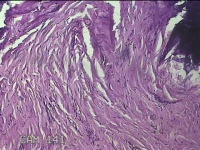

右颈部皮肤肿物

性别

女

年龄

29岁

临床诊断

纤维瘤

一般病史

右颈部皮肤起肿物10年左右。

标本名称

大体所见

灰白暗红色肿物0.3x0.2x0.1cm一个,表面光滑。

图1